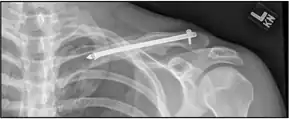

| X-ray of a left clavicle fracture | |

The basic method to check for a clavicle fracture is by an X-ray of the clavicle to determine the fracture type and extent of injury. In former times, X-rays were taken of both clavicle bones for comparison purposes. Due to the curved shape in a tilted plane X-rays are typically oriented with ~15° upwards facing tilt from the front. In more severe cases, a computerized tomography (CT) or magnetic resonance imaging (MRI) scan is taken. However, the standard method of diagnosis through ultrasound imaging performed in the emergency room may be equally accurate in children.[5]